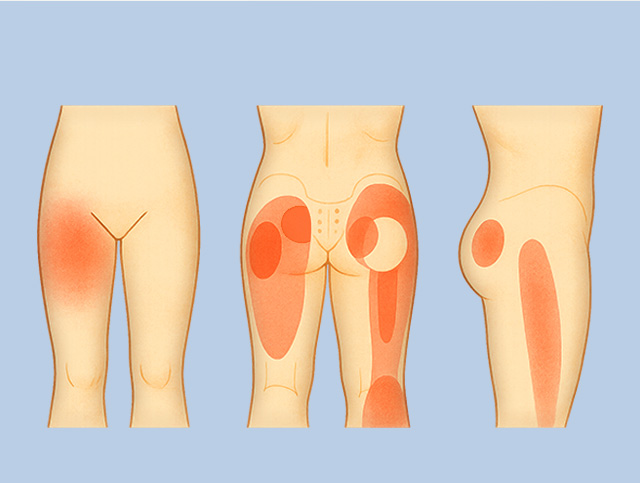

좌골신경통

좌골 신경에 염증, 손상, 압박이 발생하여 허벅지, 종아리, 발로 이어지는 통증

허리디스크나 척추관협착증, 이상근 증후군이나 근근막통증 증후군에 의한 발생이 많은 편